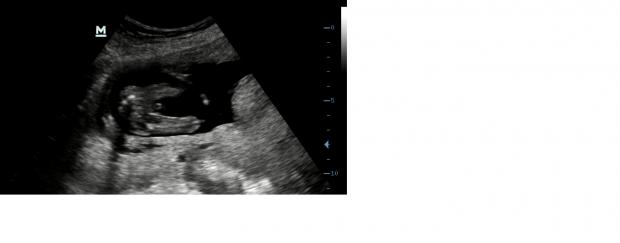

Hi everyone

I share four pictures and a video. The video is filmed from the underside of the baby.

Please, does anyone know, I really have no idea?